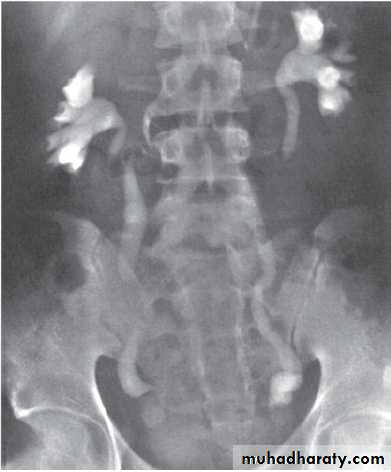

MCUG

The VCUG:

the definitive examination

to diagnose and grade reflux and establish reversible causes

must include a voiding phase:

in some cases, reflux may be seen only during the elevated intravesical pressures associated with micturition.

in visualizing the urethra, may allow the diagnosis of outflow obstruction to be made (e.g., posterior urethral valves).

Grading of VUR

The degree of reflux is graded I–V.Grading is based on the appearance of contrast agent in the collecting system during voiding cystourethrography (VCUG(.